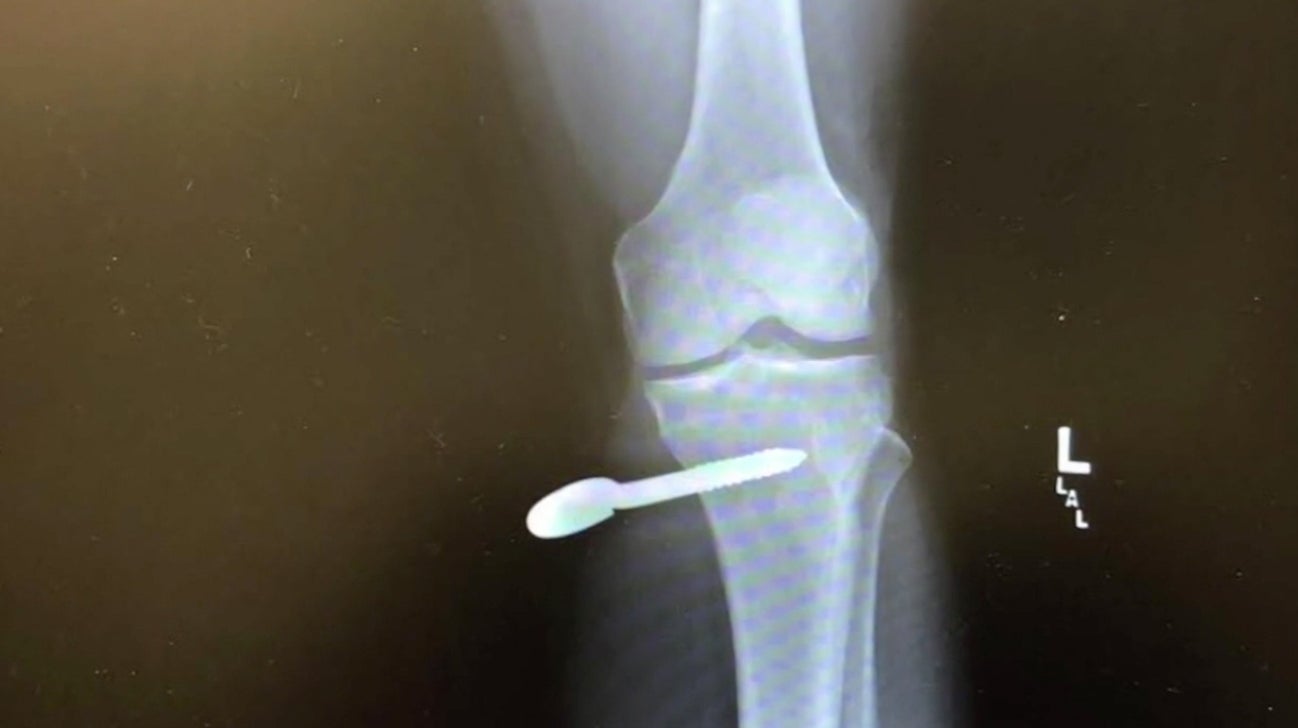

The golfer, Matt Gutierrez, was taking practice swings with his wedge when the clubhead caught a rope line that was pinned to the ground with bolts, according to a report by KVDR, a Fox affiliate in Colorado. The force of his swing ripped one of the bolts out of the ground and sent it spiraling into Gutierrez’s leg, piercing his bone.

Gutierrez was rushed to a hospital where doctors unscrewed the hardware.